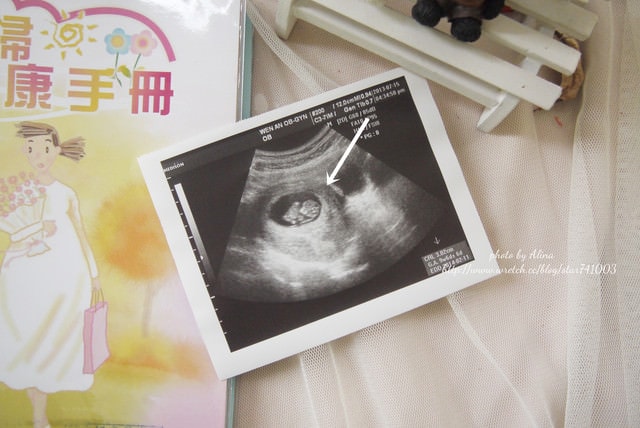

不過自從八周寶寶開始有心跳後我的身體狀況開始大改變

8~10周的時候很會睡,睡到我看到床都會怕而且完全無法工作